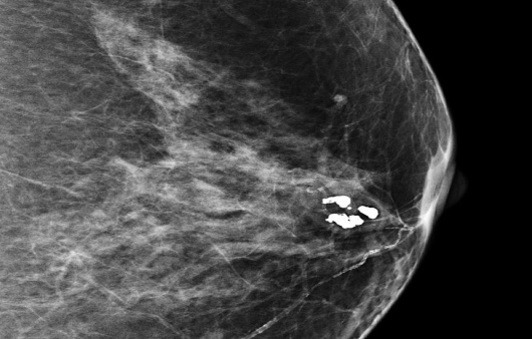

양성 미세석회화의 특징

양성 미세석회화는 다음과 같은 특징을 가집니다.

- 크기가 비교적 크고 둥근 형태

- 모양이 규칙적이고 균일함

- 분포가 산재되어 있음

- 대개 양측성으로 나타남

- 시간이 지나도 크기와 모양의 변화가 거의 없음

양성 미세석회화는 유방 조직의 자연적인 노화 과정, 유방 낭종, 섬유선종, 유선증, 유방염 등 다양한 양성 질환에서 발생할 수 있습니다. 이러한 경우에는 암과 관련이 없어 별다른 치료 없이 정기 추적관찰만으로 관리가 가능합니다.